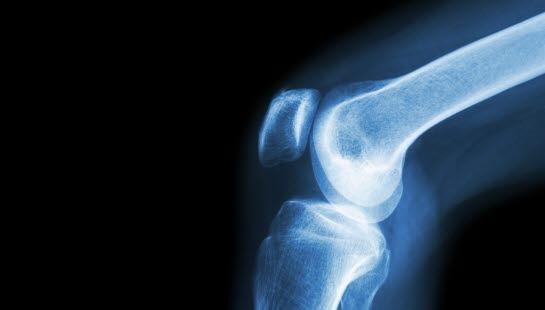

Kalsiumpyrofosfat-avleiringer er en vanlig tilstand hos eldre der kalsiumpyrofosfat-krystaller avleires i ledd eller leddnære strukturer. Krystallene avleires først og fremst i bruskstrukturer rundt og i ledd. Tilstanden kalles da kondrokalsinose. Årsaken til krystallavleiringene er ukjent, men disponerende faktorer er arv, tidligere leddskade samt enkelte sykdommer. Krystallavleiringer kan ses på et røntgenbilde uten at personen har symptomer. Kondrokalsinose kan forårsake utfelling av krystaller i leddvæsken og gi smertefulle leddbetennelser som likner på urinsyregikt. Diagnosen stilles ved påvisning av slike krystaller i leddvæsken og behandlingen er da smertestillende og betennelsesdempende medisin eller en injeksjon av kortison i leddet. Det finnes også forebyggende behandling. De fleste med kalsiumpyrofosfatavleiringer forblir uten symptomer.

Pyrofosfat-avleiringer rundt ledd kan vises på røntgen eller ultralyd og være uten symptomer. Ved leddbetennelse vil senkningen være forhøyet. Å stille diagnosen krystallartritt krever sikker påvisning av kalsiumpyrofosfat-krystallene i leddvæsken. Akutt leddbetennelse i skulder eller albue og debut i høy alder kan gi mistanke om denne typen betennelse.